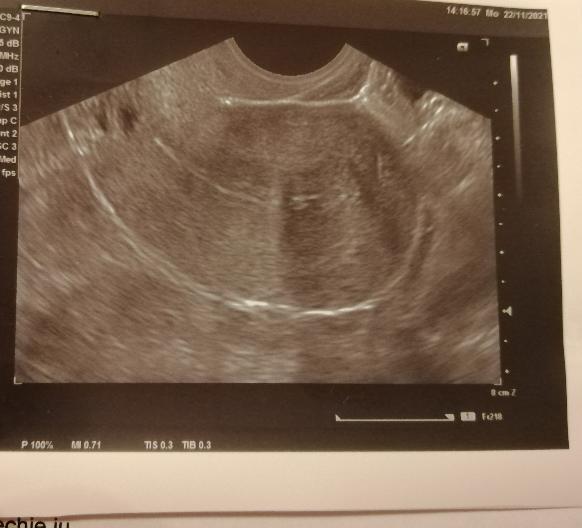

bola som na sono. Doktor mi vytlačil obrázok, čo nikdy neurobil. Nič mi nepovedal. Čaká ma hysteroskopia, lebo mám zrasty v maternici aj v brušnej dutine. Boli zistené, ale neodstránili ich. Tak idem ešte raz na HSK. Následne ma čaká umelé oplodnenie.

Čo vidíte na fotke zo sona?

na fotke je viditeľná maternica v pozdĺžnom reze aj so sliznicou maternice, ktorá sa zdá byť na prvý pohľad nižšia a nepravidelná. Čo by mohlo naznačovať prítomnosť zrastov. Definitívna diagnóza a jej rozsah sa však určí hysteroskopiou.